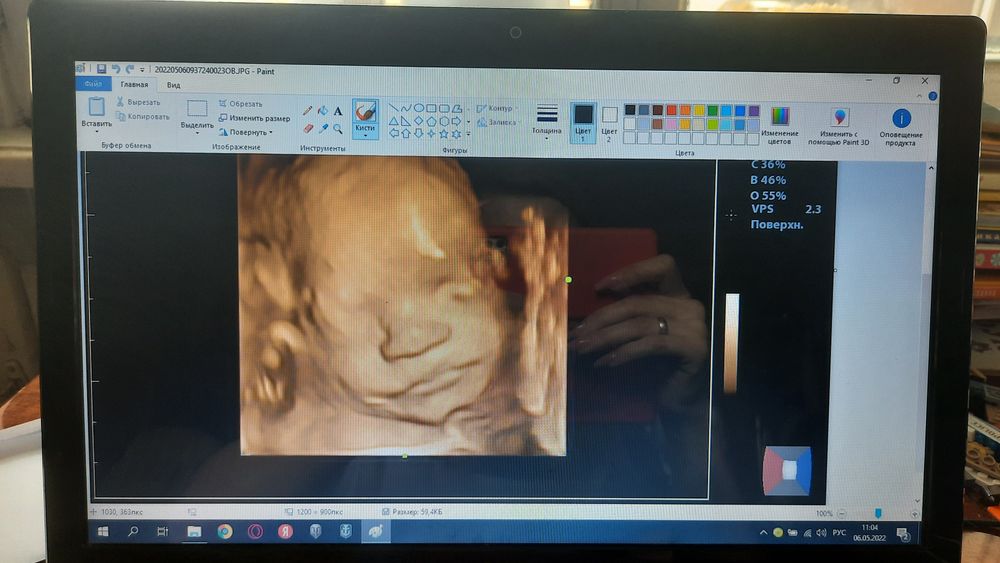

Фото в 26 недель. Отлично видно, родился очень похож. Ещё ходила в 32, но уже было плохо видно